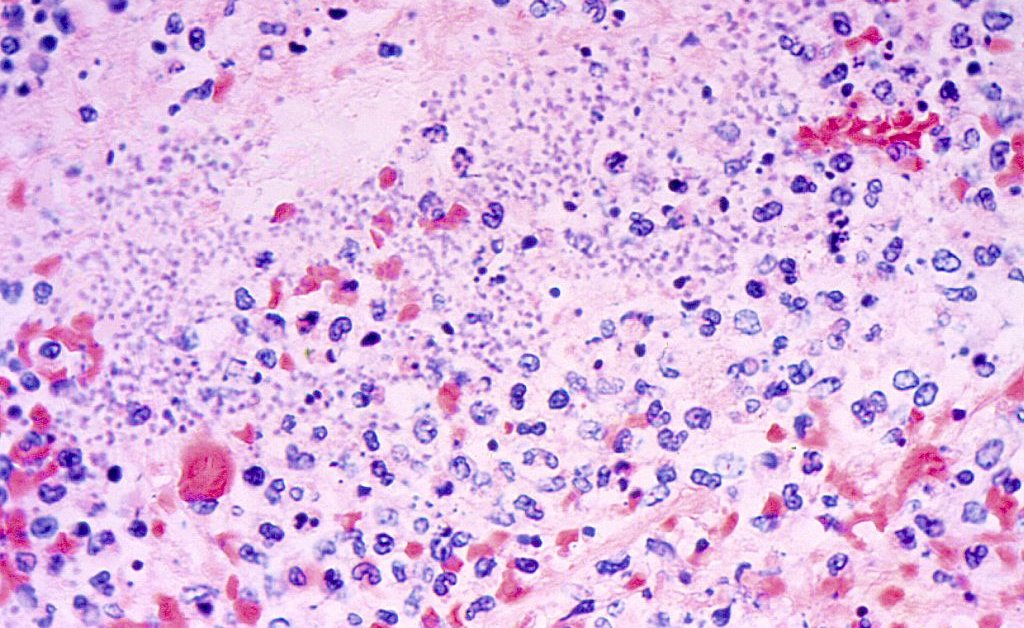

Pneumonische Pest, die auftret Cleveland Clinic.

Pneumonische Pest ist die einzige Artwork von Pest, die laut dem von Individual zu Individual übertragen werden kann US -Zentren für die Kontrolle und Prävention von Krankheiten (CDC). Laut der Cleveland Clinic kann durch Husten und Niesen eine Übertragung von Individual zu Individual durch Husten und Niesen stattfinden. Eine Individual könnte aber auch die Krankheit nach engen Kontakt mit einem mit ihm infizierten Tier oder von Bakterien bekommen, die sich von einem anderen Körperteil zur Lunge bewegen.